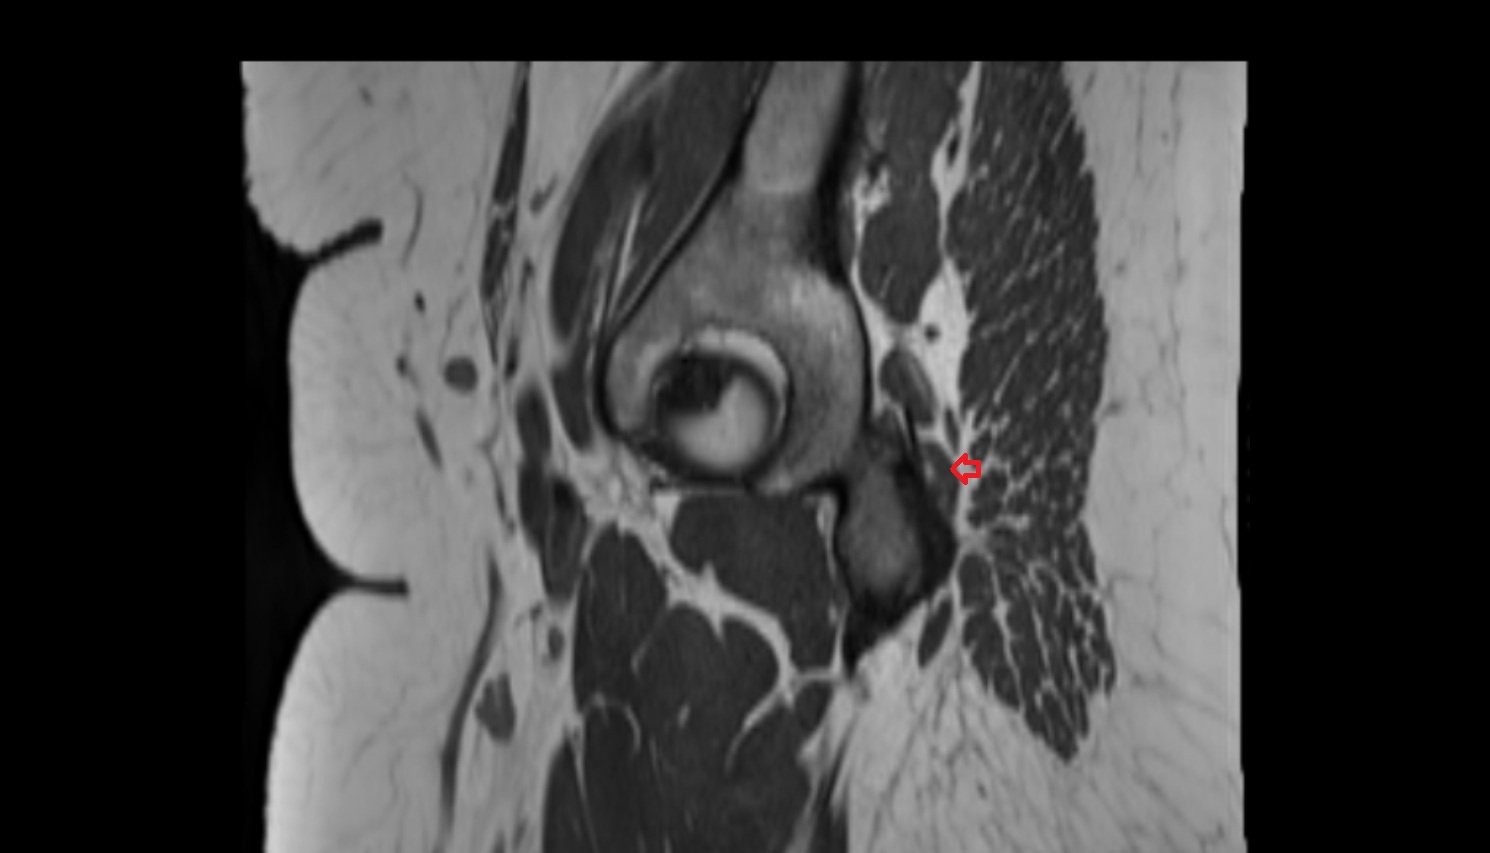

- Hip joint